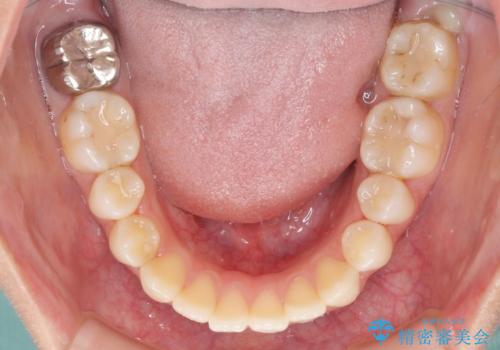

- オープンバイトのため、話しているときの見た目が気になるとのことで来院された患者様です。

下顎骨は左側にシフトしており、咬み合ったときには奥歯と前歯の一部しか接触していない状態でした。

骨格的な左右差は歯列矯正は改善できないため、上下歯列が全体的に接触することをゴールとしてインビザラインにて矯正治療を行うこととしました。

前歯のデコボコの解消と並行して上下の奥歯を圧下させるようにすることで、前歯を接触させるように計画しました。